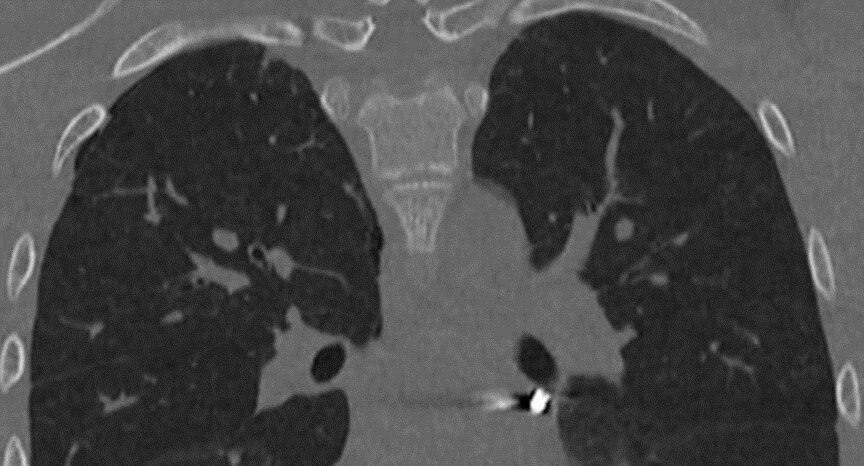

Врачи Детского клинического центра имени Л. М. Рошаля спасли 16-летнего пациента с ранением грудной клетки. Травма, полученная во время неосторожных игр с пневматическим ружьем, оказалась крайне опасной — при обследовании врачи обнаружили, что инородное тело расположилось в непосредственной близости от сердца. Врачи выполнили малоинвазивную операцию. Они вскрыли перикард и вынуждены были работать в миллиметре от важнейших для жизни структур. «Особую сложность представляла необходимость манипулировать инструментами в условиях ограниченного обзора и постоянного движения сердца. В ходе вмешательства нам удалось извлечь инородное тело без единого разреза», — поделился деталями сложнейшей операции заведующий отделением детской хирургии № 2 Никита Степаненко. Благодаря мастерству хирургов вмешательство завершилось успешно — подросток полностью восстановился, его уже выписали из медицинского учреждения. Этот случай вновь напоминает о важности ответственного отношения к выбору развлечений и не

Врачи Детского клинического центра имени Л. М. Рошаля спасли 16-летнего пациента с ранением грудной клетки. Травма, полученная во время неосторожных игр с пневматическим ружьем, оказалась крайне опасной — при обследовании врачи обнаружили, что инородное тело расположилось в непосредственной близости от сердца.

Врачи выполнили малоинвазивную операцию. Они вскрыли перикард и вынуждены были работать в миллиметре от важнейших для жизни структур.

«Особую сложность представляла необходимость манипулировать инструментами в условиях ограниченного обзора и постоянного движения сердца. В ходе вмешательства нам удалось извлечь инородное тело без единого разреза», — поделился деталями сложнейшей операции заведующий отделением детской хирургии № 2 Никита Степаненко.